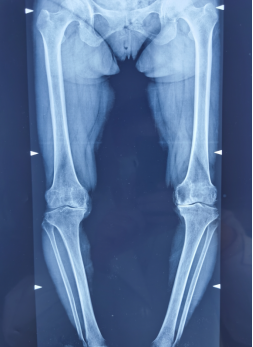

双侧膝关节已严重变形